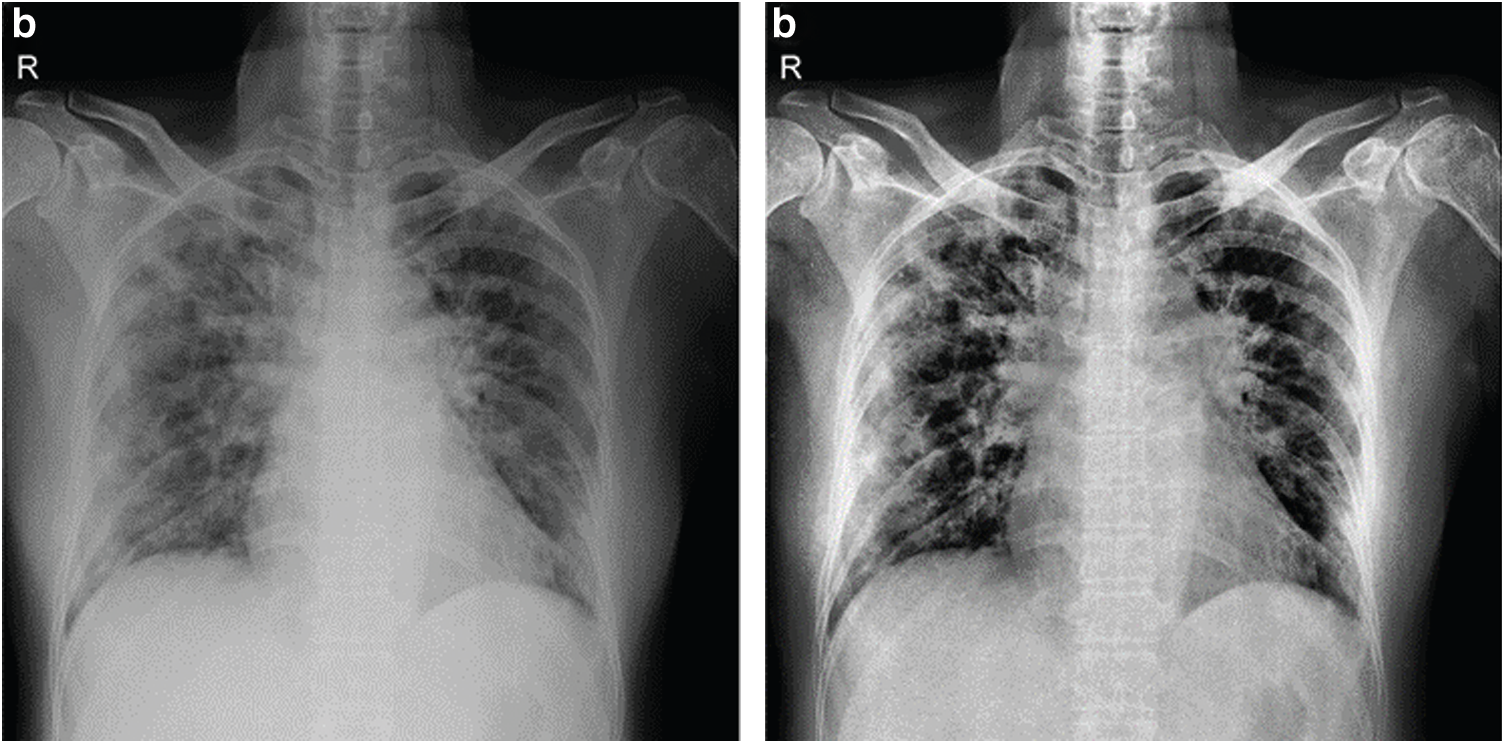

In work done on improving contrast for images in X-ray imaging, low-level exposure is maintained until the scanning process for the region of interest (ROI) is completed. Hence, the images so-obtained are often with a low signal-to-noise ratio. It is now clear that all the X-Ray images are needed to be combined in contrast. Therefore, the Contrast Limited Adaptive Histogram Equalization (CLAHE) is used before training over the dataset's input images. In Contrast Limited Adaptive Histogram Equalization, contrast amplification is limited due to the adaptive histogram equalization. This algorithm is applied to an X-Ray image by dividing the image into equal size as in Fig. 5.

Figure 5: Shows original x-ray image on left and CLAHE processed image on right

It has been observed that applying CLAHE to images before training improves the model-performance measurements (accuracy, sensibility, specificity) by a considerable amount. This can be realized from Tab. 3. Also, since ResNet101, a much deeper network than the VGG-Net, is used, the image size was set to be larger, i.e., [512, 512]. This model was implemented on MATLAB; a part of the code for reference can be read in Fig. 6. Extensive data augmentation techniques like randomly flipping, cropping, and photo-metric distortion, are also used.